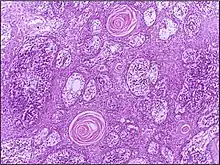

![]() | Squamous cell carcinoma of lung | Micrograph of squamous Cell Carcinoma Lung. A lobule of polygonal squamous cells with moderate amount of eosinophilic cytoplasm and hyperchromatic nuclei are seen. The islands show abnormal keratinization in the form of epithelial pearls in the centre. These epithelial pearls are whorls or eddies of malignant cells with pink keratin in the centre. | Category: Histopathology of squamous cell carcinoma of the lung | Squamous cell carcinoma of lung |